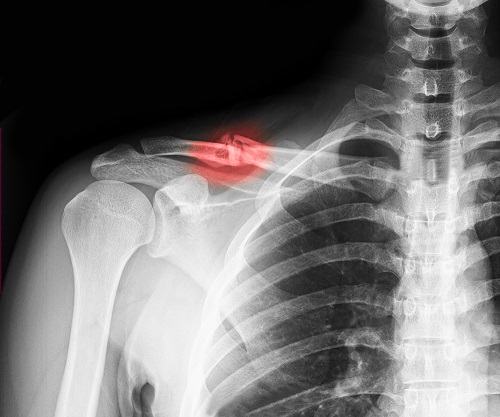

Ảnh chụp X-quang một người bị gãy xương đòn

- Nếu nghi ngờ xương đòn bị gãy, các bác sĩ sẽ khuyên bạn nên chụp X-quang vai để chẩn đoán thêm. Hình ảnh chụp X-quang có thể hiển thị hình ảnh của xương đòn bị gãy và mức độ nghiêm trọng của nó hoặc xương khác có bị gãy hay không.